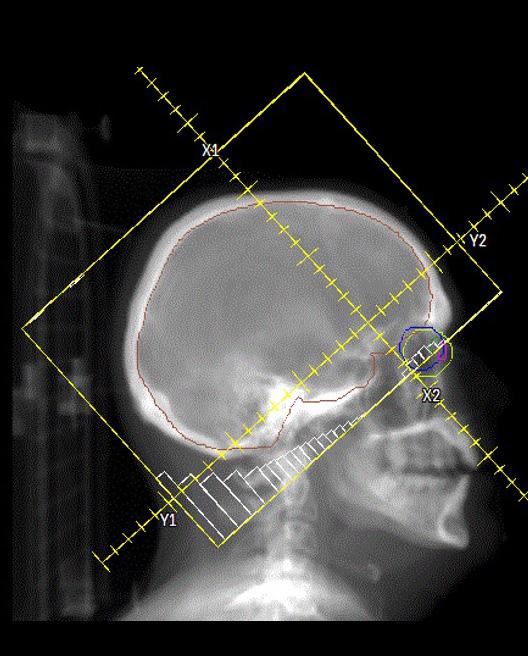

Radiooncologie

LES AVANCÉES TECHNOLOGIQUES ET LA VISION DE NOTRE ÉQUIPE MÉDICALE A PERMIS D’OFFRIR UN TRAITEMENT DE POINTE AUX PATIENTS DE NOTRE RÉGION

Quiconque travaille en radio-oncologie vous dira que les innovations technologiques sont chose commune. L’augmentation de la vitesse des calculs grâce à l’informatique y est pour beaucoup. Il n’y a pas si longtemps encore, on validait les temps d’irradiation avec des calculs manuels en un point, directement à la salle de traitement.